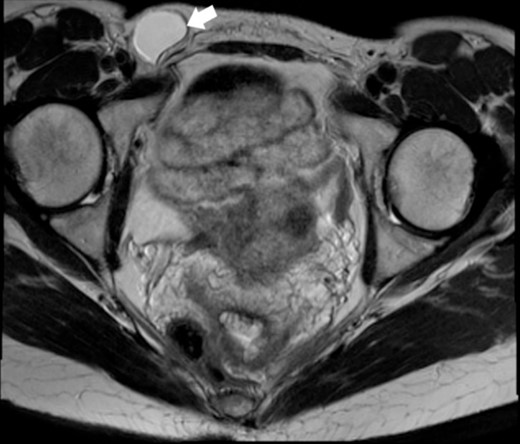

A 44-year-old Caucasian woman presented in our clinic with a painless swelling in the right inguinal region that appeared 10 months before her hospitalisation. A small soft mass measuring 4 × 2 cm2 was found on the physical examination. There were no changes in size or shape in the lesion when performing the Valsalva manoeuvre. Magnetic resonance imaging (MRI) showed an oval cyst measured 3.9/2.6/2.4 cm close to the uterus’s round ligament in the right inguinal channel. The lesion was hypointense in T1- (Fig. 1) and hyperintense in T2-sequence (Fig. 2). An anechoic cyst was observed using ultrasound. The cyst was classified as type I based on Counseller and Black’s classification [2]. Blood analysis showed no pathological changes.

MRI of the Cyst of the Canal of Nuck–T1 sequence. This image highlights the cyst (indicated by the white arrow) within the inguinal region.